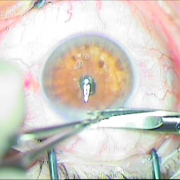

Sun Set Syndrome

πίσω από την ίριδα

ζώνης 5 ωρών

φακού